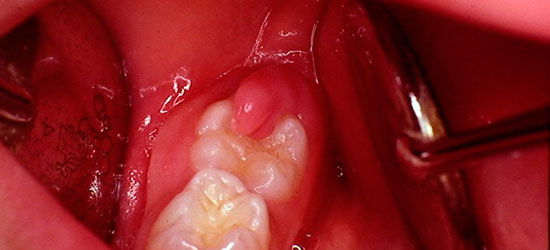

Обычно заболевание начинается с появления ноющих болей в области прорезывающегося зуба. Через 2-3 дня боли приобретают острый характер. Жевание на пораженной стороне становится невозможным или затрудненным, может появляться болезненность при открывании рта, глотании. Увеличиваются поднижнечелюстные лимфатические узлы, становятся болезненными при ощупывании (на стороне поражения). Общее состояние удовлетворительное. Причинный зуб наполовину или полностью покрыт отечным и воспаленным десневым «капюшоном», из-под которого выделяется гной. Прикосновение к такому «капюшону» вызывает сильные болевые ощущения. Боль «стреляет» в висок, ухо, верхнюю челюсть. Может повышаться температура тела (до 37-37,5⁰С), появляется головная боль, недомогание.

Слизистая оболочка вокруг зуба красная, отечна. Воспалительный процесс распространяется на щеки, слизистую оболочку небно-язычной дужки. Может произойти смещение зуба в щечную или язычную сторону, а также наклон зуба вперед.

Лечение заключается в устранении воспалительных явлений. С этой целью иссекают слизистую оболочку, которая прикрывает коронку зуба. После стихания воспалительного процесса решается вопрос о судьбе зуба. Если имеется достаточно места в зубном ряду, коронка зуба освобождена от слизистой оболочки, зуб находится в правильном прикусе с антагонистом, лечение зуба считается успешным.